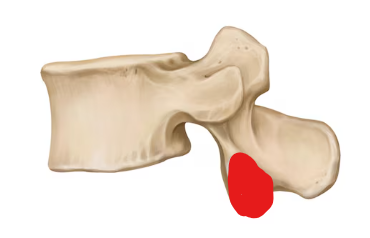

Lumbar vertebra

Superior articular process

Transverse process

Inferior articular facet

Superior articular facet

Lamina

Pedicle

Vertebral foramen